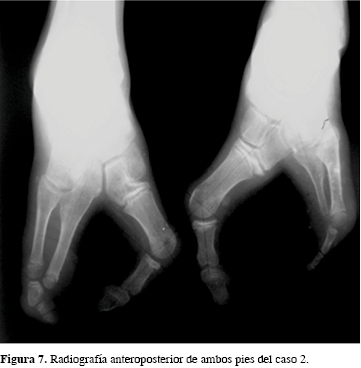

El examen físico evidenció sindactilia del cuarto y quinto dedos y hallux valgus severo bilateral (Figura 6). Radiológicamente, sólo hay tres metacarpianos y falanges en el primero y quinto dedos en ambos lados (Figura 7).

La deformidad se clasificó como una ectrodactilia tipo 2 de Abraham y grado IV de Blauth y Borisch. Como medidas de preparación para la cirugía, se utilizaron cinchas metatarsales y separadores de dedos. Posteriormente, se realizó la corrección quirúrgica mediante la supresión de la hendidura central con sindactilias de tipo lineal. El cierre del espacio intermetatarsiano se efectuó con osteotomías de la base del primer y quinto metatarsianos y osteodesis con alambres de Kirschner (Figuras 8 y 9).